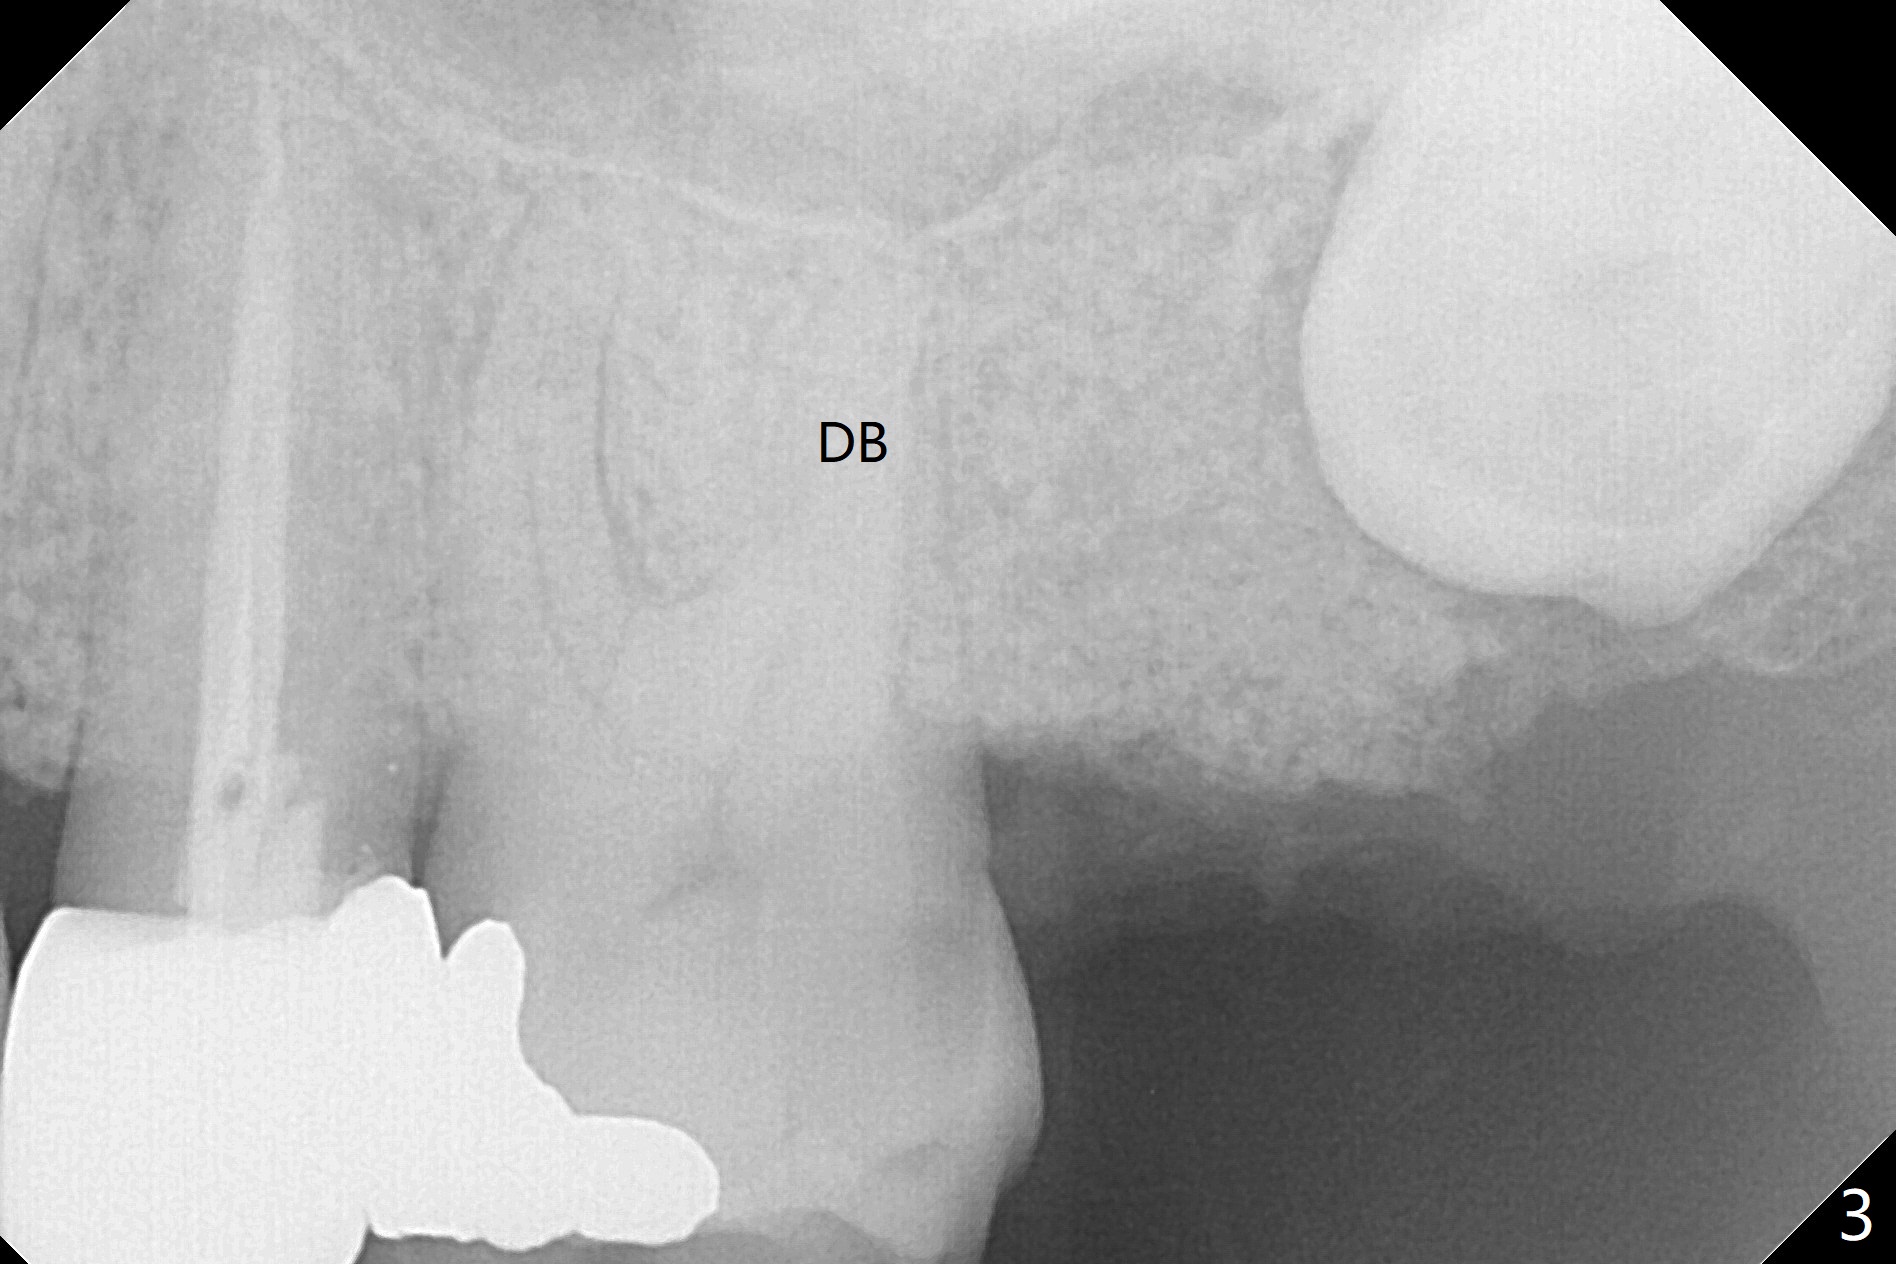

A 62-year-old man returns with acute pulpitis at #15 (Fig.1,2). The caries is confirmed subgingival after debridement. After discussion, the patient agrees with extraction and bone graft, but he does not want to have implant (Fig.3). When he changes his mind, the 3rd molar will be extracted immediately followed by implant placement with guide. Because of the narrow space, the distal surface of the distobuccal root of the 1st molar is exposed when the tooth #15 is extracted. The bone graft will prevent gingival recession of the tooth #14.